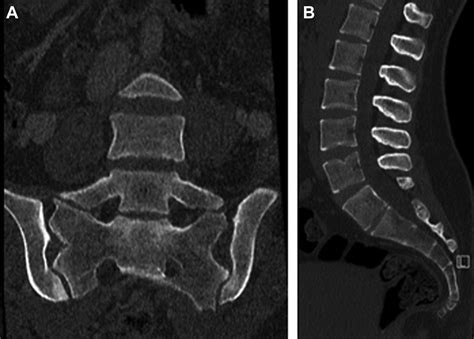

Diagnostic Imaging and Identification

Radiology plays the most critical role in diagnosing Transitional Lumbosacral Anatomy. Standard X-rays of the lumbar spine are often the first step, but they may not provide enough detail to distinguish between a fusion and a complex articulation. In more complex cases, Computed Tomography (CT) scans or Magnetic Resonance Imaging (MRI) are utilized to provide a three-dimensional view of the lumbosacral region.

Radiologists utilize a method called vertebral counting, starting from the C2 vertebra in the neck and moving down through the thoracic spine to determine the exact level of the LSTV. This rigorous process ensures that the patient's anatomy is correctly mapped, preventing miscommunication between the imaging department and the orthopedic surgeon.